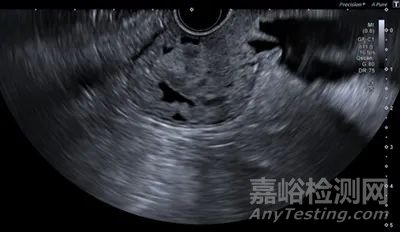

創(chuàng)新的影像技術(shù):支持快速可靠的診斷和治療。在 EUS 中,查看超聲圖像中陰影的差異非常重要。

D-THI(差分組織諧波成像)

佳能醫(yī)療開發(fā)的D-THI(差分組織諧波成像)可以獲得從淺到深區(qū)域具有足夠靈敏度的高分辨率圖像,提高組織內(nèi)部和邊界回聲的可視化能力,快速區(qū)分腫瘤和囊腫等病變與正常組織。